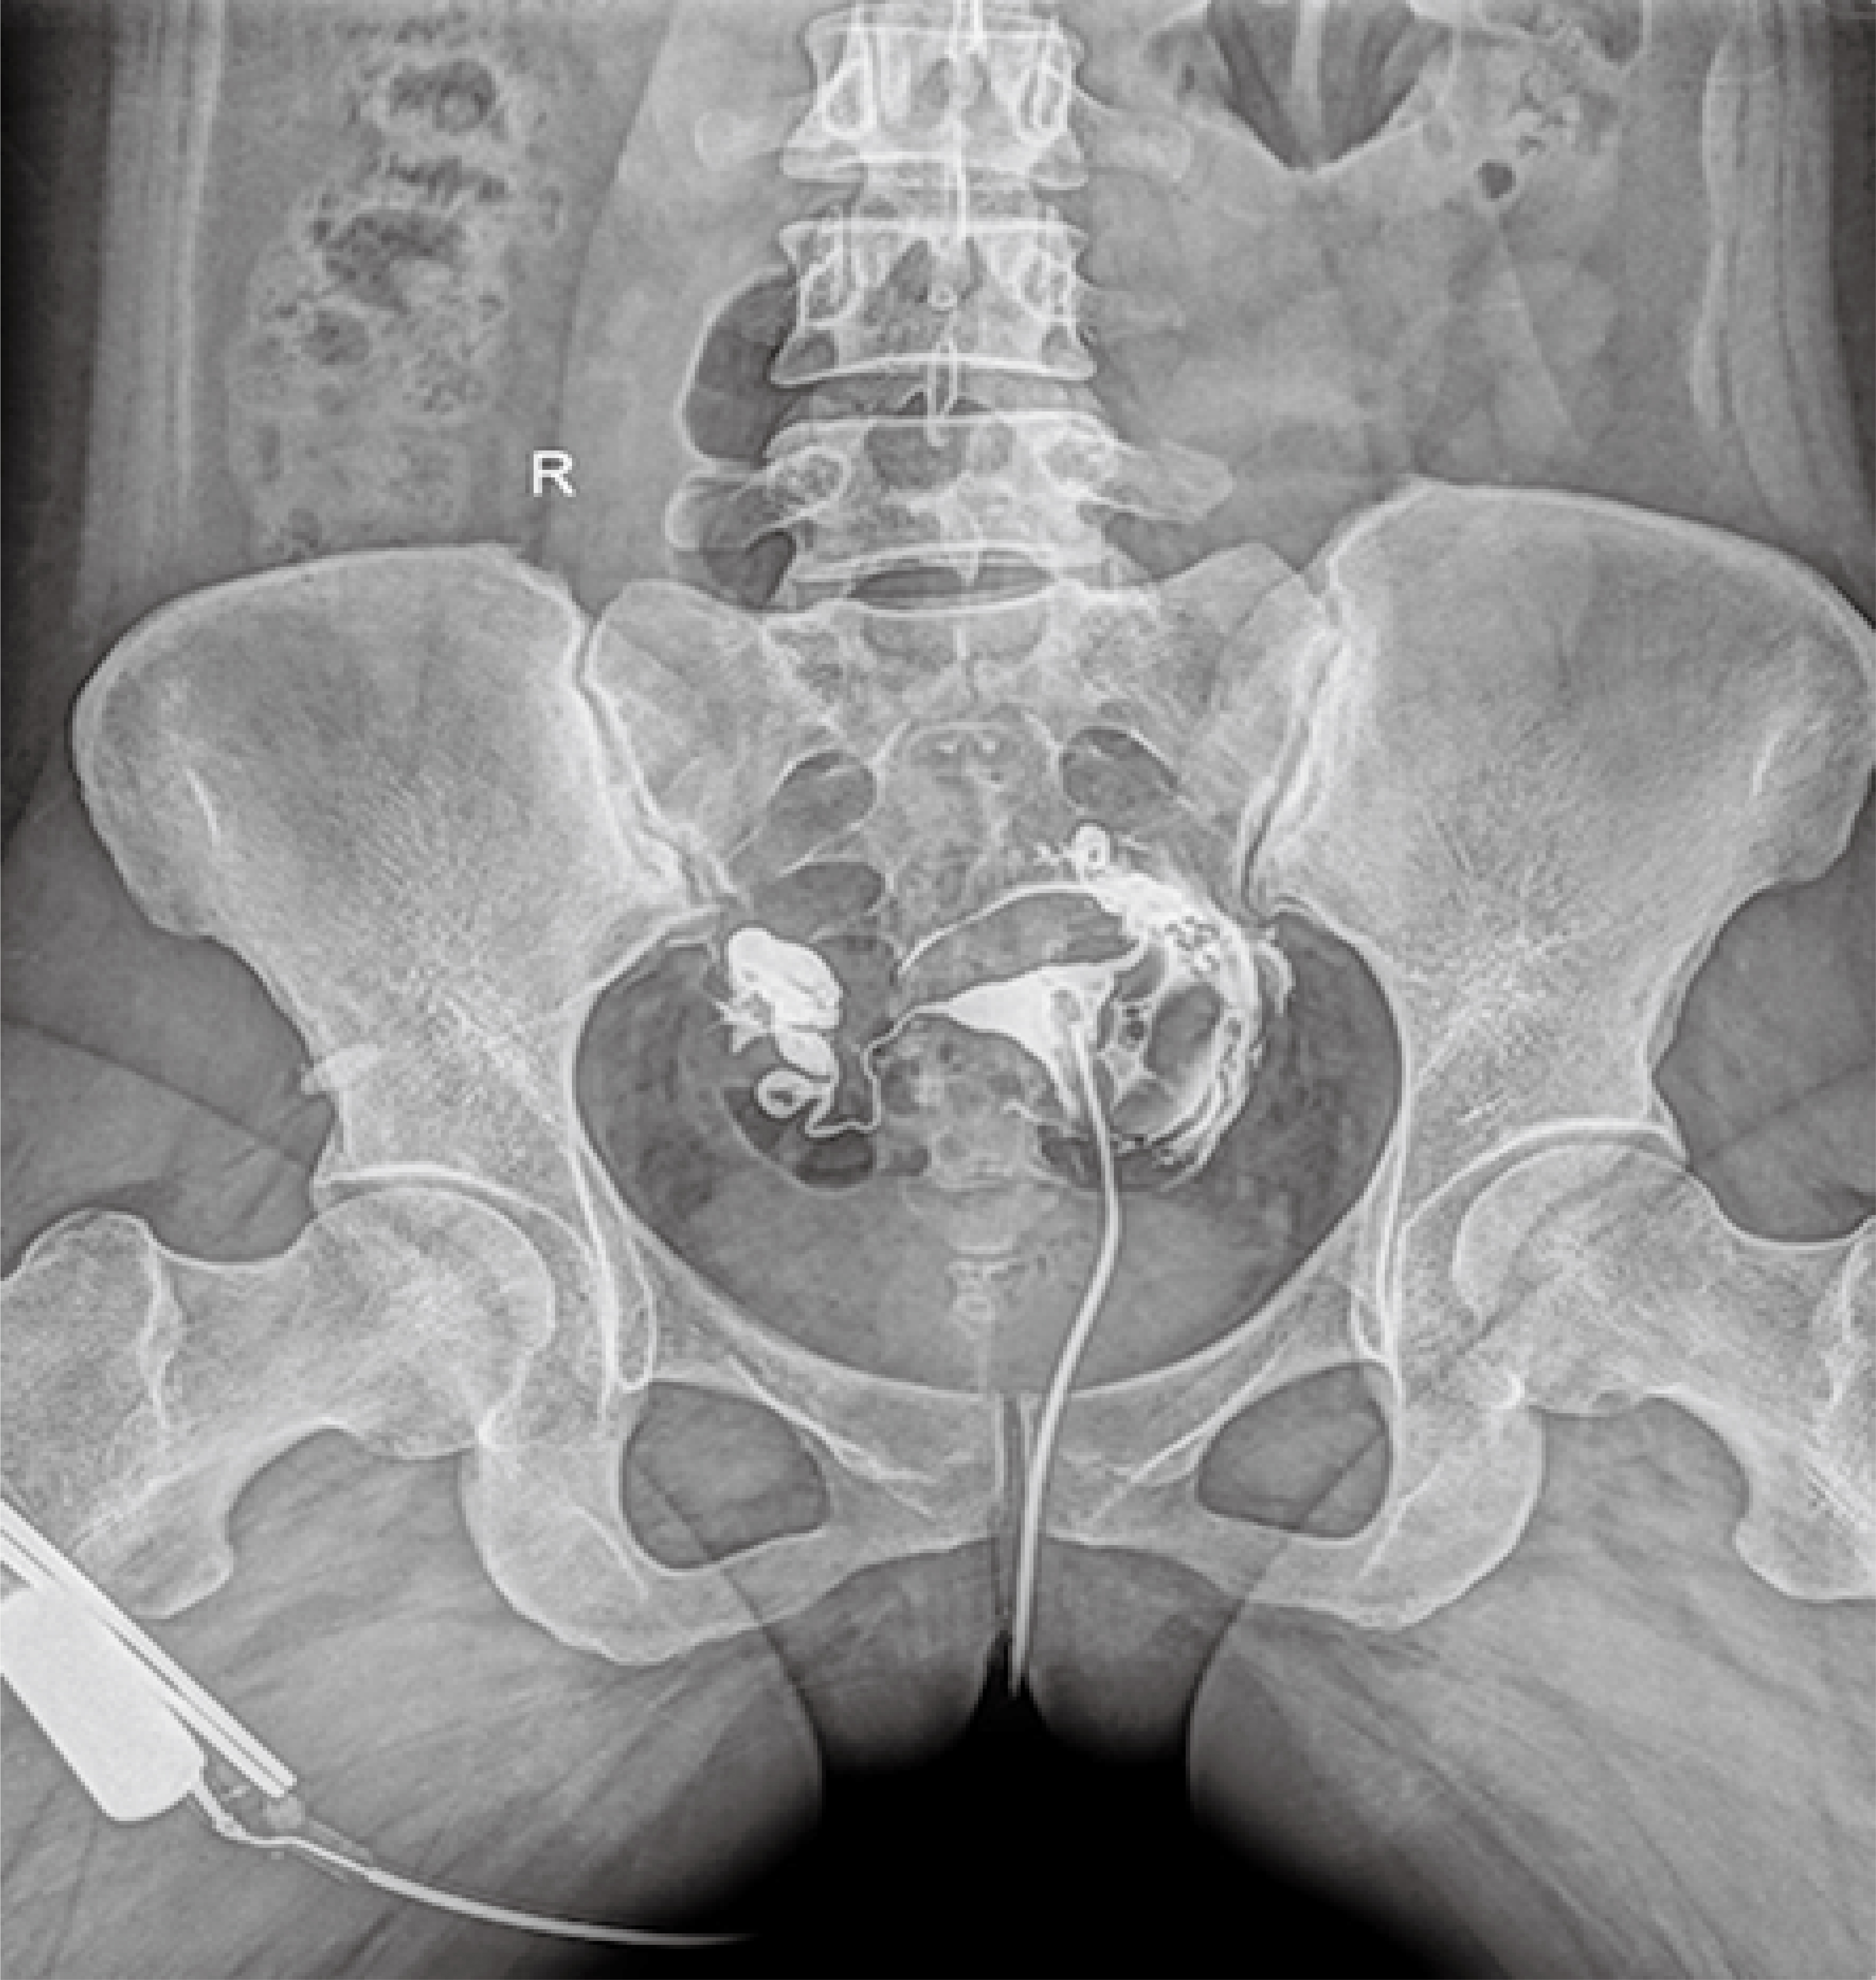

普利德醫(yī)療自主研發(fā)的新一代數(shù)字化X線透視攝影系統(tǒng),可應(yīng)用于DR攝影、數(shù)字透視、數(shù)字造影以及可視化精準(zhǔn)DR拍片等多種臨床X線檢查領(lǐng)域。

● 獨(dú)特實(shí)用的床面升降功能,有利于DR攝影及行動(dòng)不便的患者上下床;

● 床面可降至與病床平行高度,既方便醫(yī)護(hù)人員平移患者,又避免對(duì)患者的二次傷害;

● 對(duì)于醫(yī)生的近臺(tái)操作也更方便,不同身高的醫(yī)生可根據(jù)需要調(diào)節(jié)床體高度,更利于醫(yī)生開(kāi)展相關(guān)近臺(tái)手術(shù)。